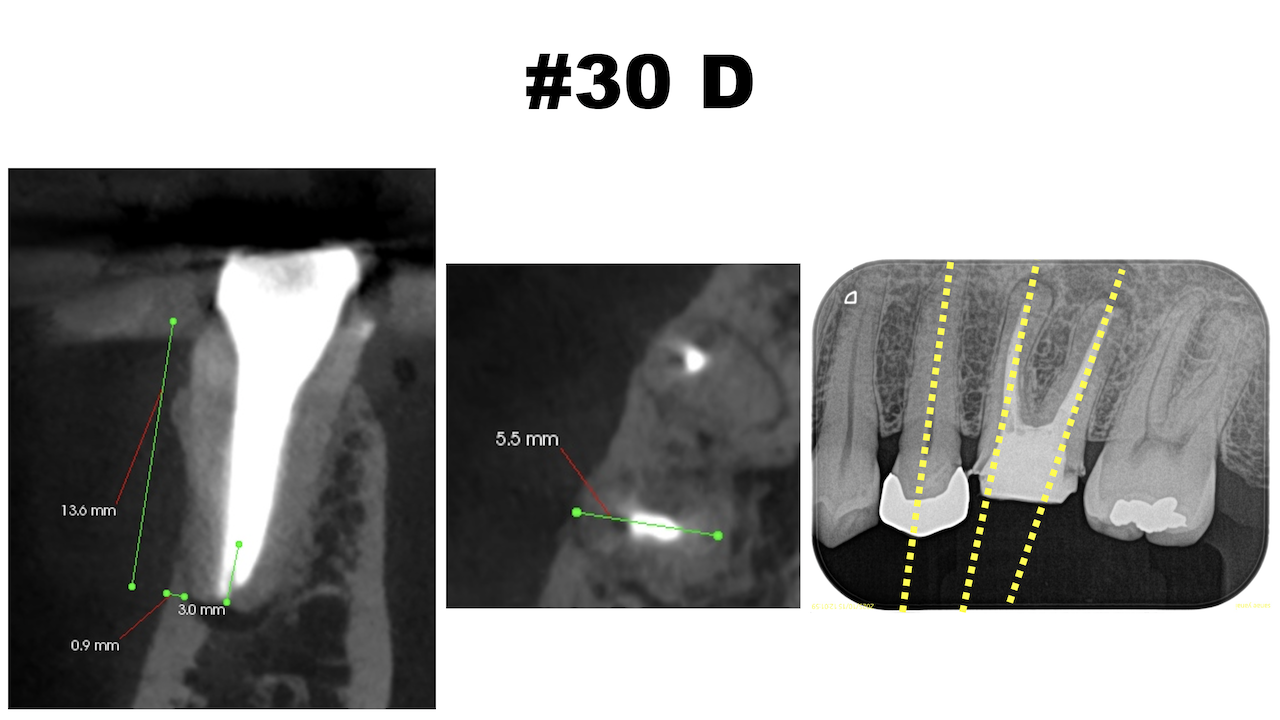

D

M,Dの根尖部には病変がある。

またMもDも形成・根充が太くなされているので治療は成功率が低いであろう再根管治療ではなくApicoectomyだ。

Recommended Tx: M,D Apicoectomy

DのApexの位置をCBCTを参考に予想し、OsteotomyしRoot resectionした。

逆根管形成し逆根管充填した。